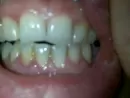

Сначала немного начала болеть челюсть в районе одного зуба, через два дня образовались гнойные, круглые ранки (убрала я их ванной палочкой), т.к. были новогодние праздники не могла попасть к стоматологу, полоскала рот ратоканом, неприятные ощущения исчезли (прекратилась боль), затем немного припухли десна — если надавливала на них выделяется белая жидкость похожая на гной, появились заезды в уголках губ.

Была у трех стоматологов, говорят полоскать содой с спит.календул., корой дуба и мазать пародонтоксом. Уже месяц делаю и ничего не помогает. Воспаление десны не проходит, так же выделяется жидкость при нажатии, боли нет, десна бледные, выборочно припухшие, около 4зубов.

Прикрепленые фото

Не знаю у каких стоматологов вы были, скорее всего это гос. поликлиника, но тут проблема налицо. Плохая гигиена и поддесневые отложения. Никакие полоскания вам не помогут, обратитесь на прием к стоматологу для комплексной гигиены полости рта.